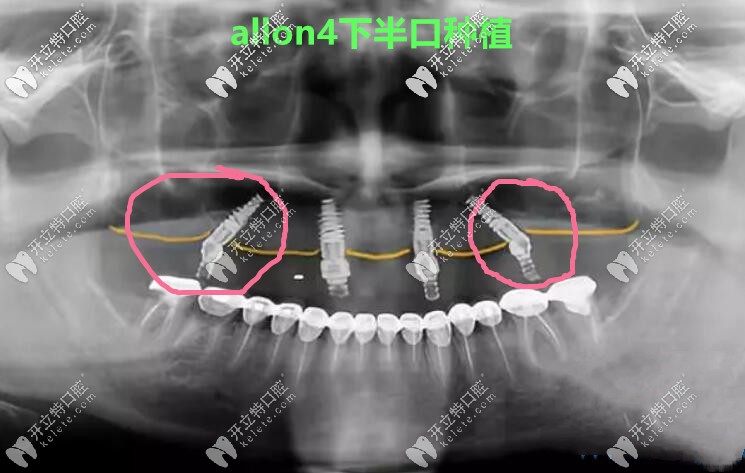

張海波院長(zhǎng)說(shuō),它倆明顯的區(qū)別就是,allon4/6有2顆植體是斜著的,因?yàn)楸荛_了神經(jīng)管和上額竇孔腔,所以主要針對(duì)的是那些牙槽骨非常糟糕,無(wú)法常規(guī)種植的人。

做allon4下半口種植牙真人案例CT照↓↓↓

做allon4下半口種植牙真人案例CT照